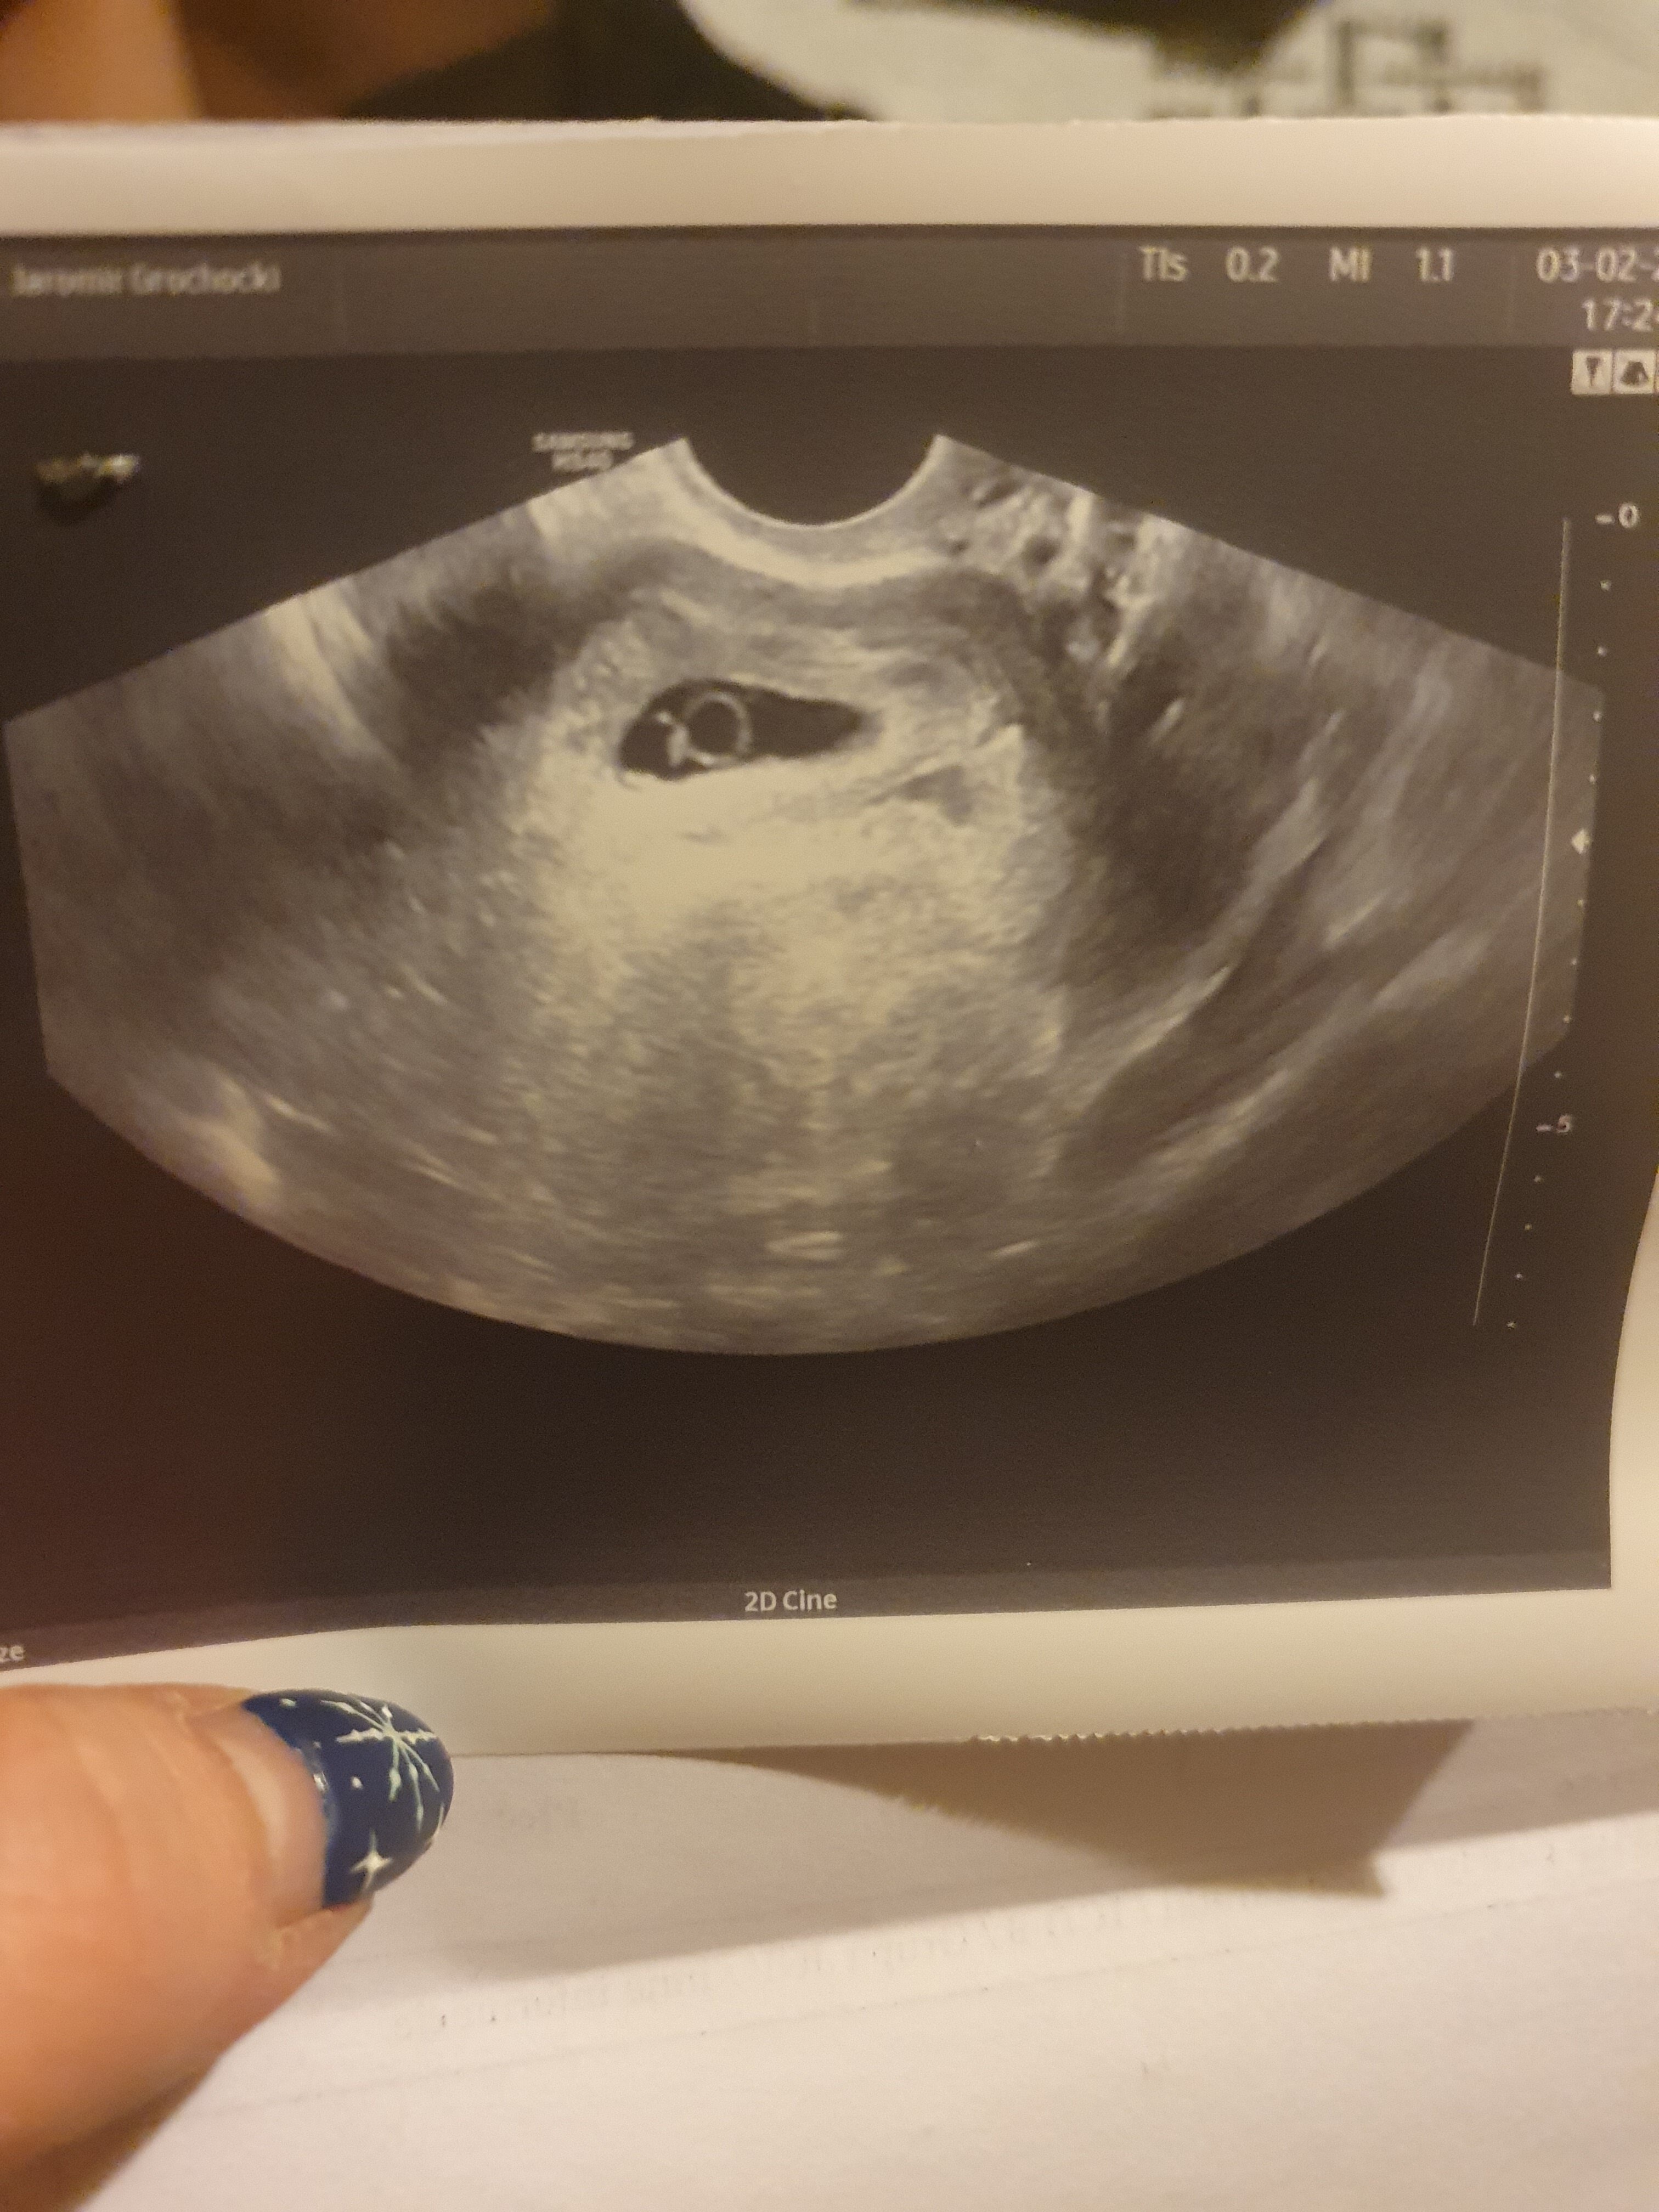

Hejka 😊😊 juz wcześniej pamietam, ze pisałam na tym forum jak starałam sie z partnerem o dziecko. Byłam potem u lekarza i przepisał mi leki które miały pomóc. Czytałam potem i w sumie od koleżanki został mi również polecony olej z wiesiołka i coś na pewno zadziałało bo w zeszły piątek (28.01.22) zrobiłam test ciażowy który wyszedł pozytywny. Powtórzylam go jeszcze raz w ten sam dzień i jeszcze dla upewnienia zrobiłam w sobote rano kolejne dwa. 4 testy pozytywne cieszylam sie bardzo. W poniedziałek byłam zrobić beta HCG wyszła ok. 40 tys. We wtorek bylam u ginekologa, który nie zrobił mi żadnych badan kazał czekać i przyjść za 3 tyg. Jednak ja zadzwoniłam i umówiłam sie do innego lekrza. W środę bylam znowu na pobraniu krwi w celu sprawdzenia bety wynik byl mniejszy bo tylko 14 tys. Dzisiaj (03.02.22) bylam u lekarza który zrobił mi usg na którym niestety nie ma zarodka 😔😔😔 dal skierowanie do szpitala na 7.02.22. Nie wiem dlaczego beta tak spadla lekarz też nie jest pewny dlaczego az tak skoro byla wysoka a teraz taka mala. Może któraś z was miała podobny przypadek i jest mi wstanie pomóc czy decydować sie na zabieg czy lepiej jeszcze poczekać wg usg 6/7 tydzień wiele kobiet pisało, ze zarodek byl widoczny u nich okolo 8/9 tyg. Sama nie wiem co mam o tym myśleć nastawiłam sie troszke juz na dzidziusia. Dołączam moje zdjęcie USG

• 20220203_182849.jpg

20220203_182849.jpg

1,4 MB · Wyświetleń: 293

Oo pamiętam cie z wpisów odnośnie zajściem w ciążę 🙂 Pisałyśmy o wiesiołku. A powiedz mi czy beta była robiona w takim samym laboratorium? Jednostka miary była taka sama? Kiedy miałaś ostatnio miesiączkę? Beta zdecydowanie może słabo rosnac ale nie powinna spadać natomiast mój lekarz zawsze powtarzał ze powyżej bety 6000 liczy się obraz usg a nie beta. Pęcherzyk nie jest pusty , widać w nim pięknie pęcherzyk żółtkowy. Czasami brakuje dnia żeby pojawił się zarodek.

Masz regularne cykle? Jeśli ostatnia miesiączka była 1 grudnia to wyszedłby 10 tydzień ciąży a patrząc na usg to niemożliwe. Dostałaś może zdjęcie usg z wielkością pęcherzyka? Ja bym jeszcze poszła do innego ginekologa z dobrym sprzętem. Zarodek z reguły pojawia się na dniach jeśli jest pęcherzyk żółtkowy- wtedy będziesz wiedzieć na czym stoisz.